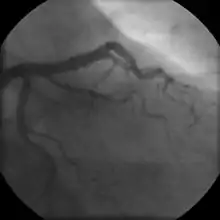

- Coronary angiography